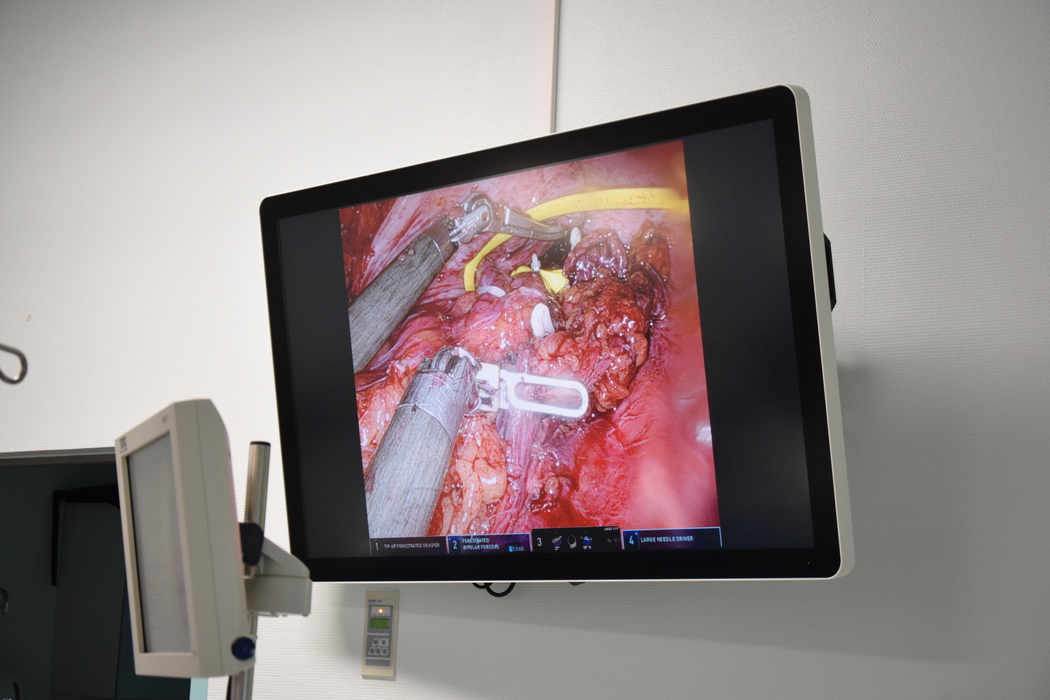

- Ponieważ chory był wcześniej leczony onkologicznie, a my poczuwamy się do ciągłości opieki nad naszymi pacjentami, szukaliśmy rozwiązania tej sytuacji. Po przeanalizowaniu zaproponowaliśmy pacjentowi operację będącą połączeniem dwóch zaawansowanych technik chirurgicznych. Uznaliśmy, że przy ich jednoczasowym połączeniu chory zostanie skutecznie zoperowany z powodu dwóch współistnienie problemów: zwężenia zespolenia skutkującego kłopotami z wypróżnianiem oraz polipa czyli nowotworu łagodnego – tłumaczy chirurg. - Dostęp do tej okolicy był trudny, dlatego od strony brzucha zastosowaliśmy chirurgię robotyczną, która daje nam największą precyzję i powiększenie pola operacyjnego a od strony odbytu wykonaliśmy zabieg endoskopowy w celu nawigowania. Przy pomocy robota wycięliśmy cały chory odcinek jelita, w którym znajdował się polip i zwężenie. Połączenie dwóch technik umożliwiło nam zoperowanie tego pacjenta w skuteczny i mało inwazyjny sposób – wyjaśnia dr Paweł Renkielski.